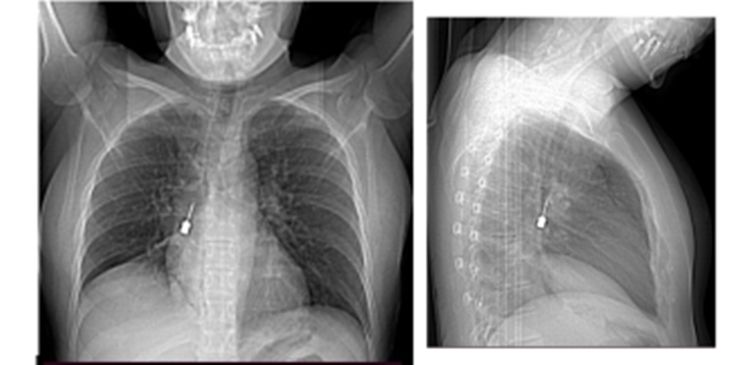

REGGIO CALABRIA Delicatissima procedura endoscopica effettuata nelle scorse settimane al Grande Ospedale Metropolitano di Reggio Calabria. Il Direttore dell’UOC di Chirurgia Toracica, Baldassare Mondello, insieme alla sua équipe, ha estratto in urgenza per via broncoscopica un cacciavite odontoiatrico accidentalmente inalato da una giovane donna. La paziente è giunta al Pronto Soccorso del G.O.M. esibendo un esame di diagnostica per immagini (Tomografia Computerizzata) eseguito a causa di una tosse persistente e di un forte dolore a livello toracico.

La TC mostrava la presenza di un corpo estraneo metallico pericolosamente incastrato nel bronco lobare inferiore del polmone destro e un concomitante pneumomediastino, ossia la presenza di aria nello spazio compreso fra i due polmoni. Prontamente ricoverata, la paziente è giunta in sala operatoria ove è stata sottoposta in urgenza all’intervento. Il decorso postoperatorio, gestito dalla validissima équipe della U.O.S.D. Terapia Intensiva Post Operatoria (T.I.P.O.) diretta dal Massimo Caracciolo, è stato regolare e la paziente è stata dimessa in ottime condizioni. Il personale che ha coadiuvato Mondello nell’intervento: Massimino Messinò (medico in formazione), anestesisti, Lilly Gatto e Leonardo Cosenza. Personale del Blocco Operatorio: CPS Fortunato Quattrone, CPS Angela Fiozzo e CPS Paolo Pennestrì. (redazione@corrierecal.it)